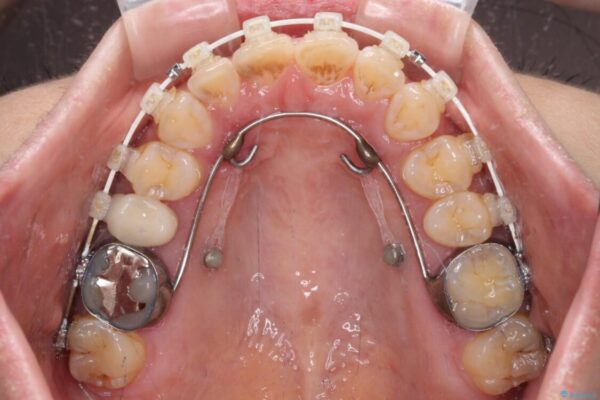

治療途中

• 【モニター】飛び出た前歯を整えたい ワイヤー矯正治療 治療途中画像

奥歯の咬み合わせは、上顎歯列が理想的な一よりも数mm前方にある状態でした。

なるべく早めに治療を終えたいとのことで、補助装置を用いて上顎臼歯を後方に移動させ、同時にワイヤー装置にて整えることとしました。